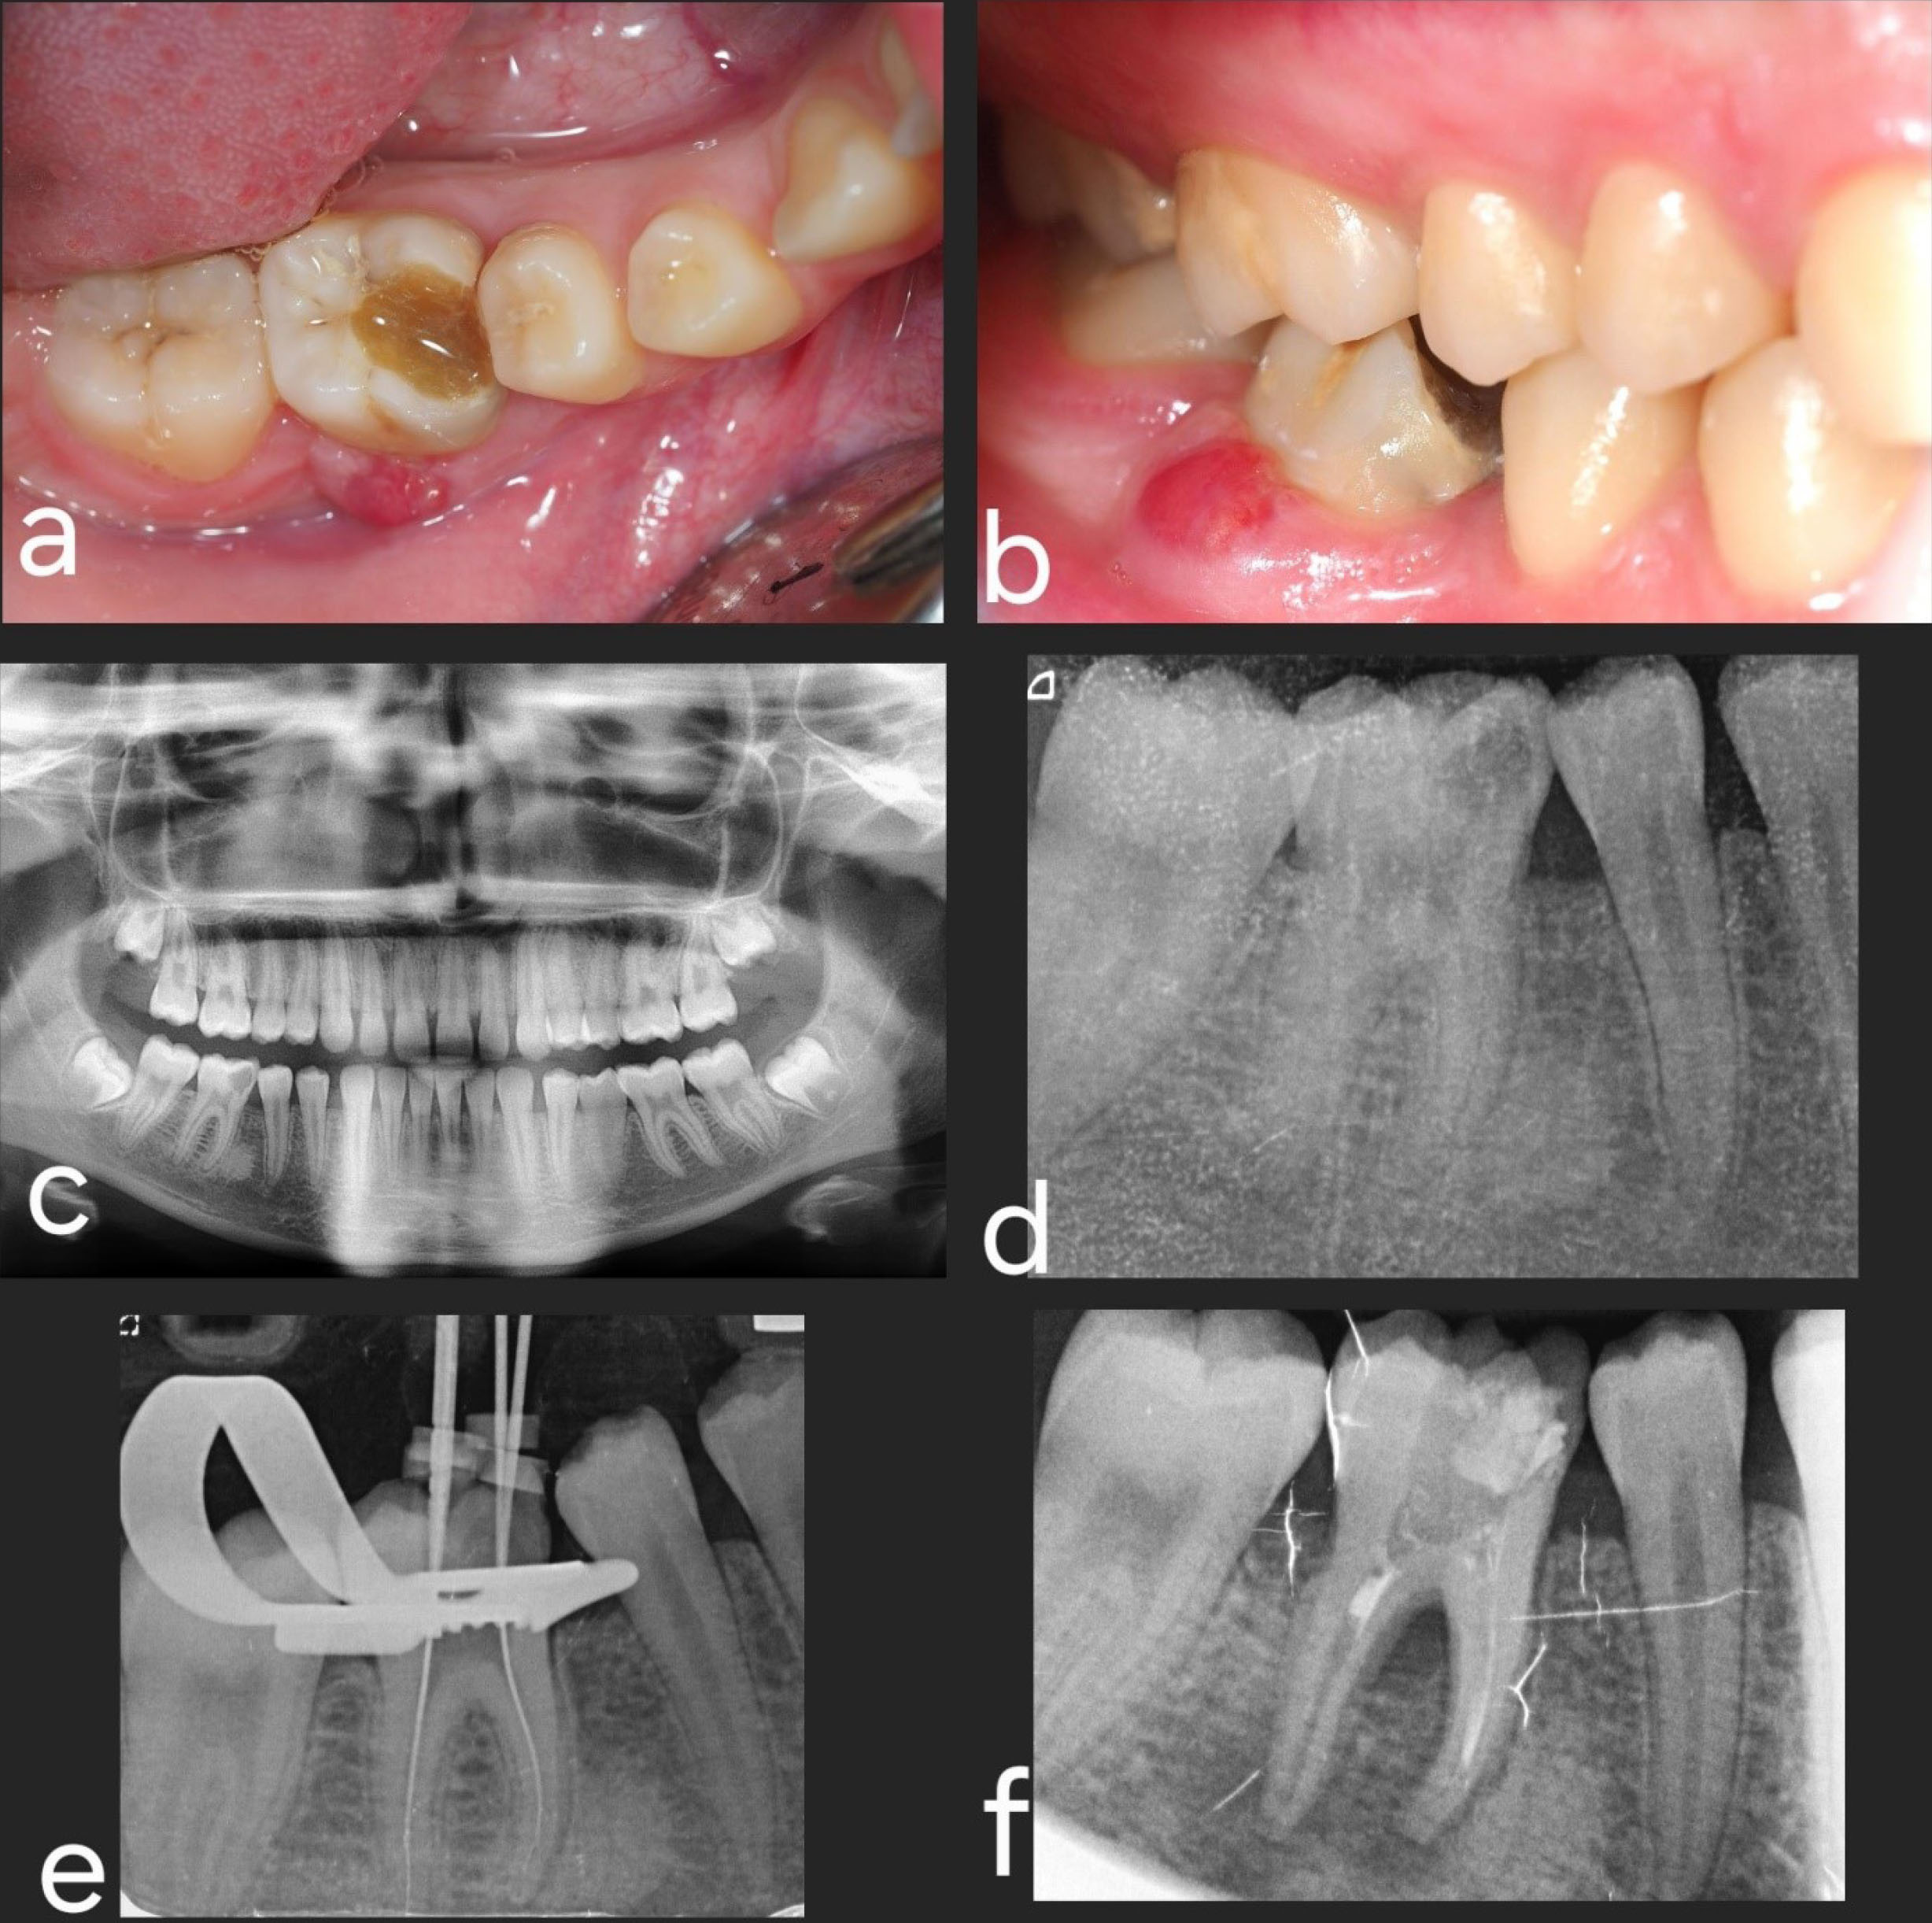

The initial postoperative period was uneventful, with no signs or symptoms of infection, pain, or swelling (Figure 6). Oral hygiene instructions were given again to the patient since some food debris was observed in the splinting area. The sutures on the third molar site were removed, and periapical radiography was performed.

Figure 6.

Follow-up. (a) One week after surgery. (b) Periapical radiograph one week after surgery. (c) Four weeks after surgery, the buccal splinting has fallen off. (d) Four weeks after surgery, the splinting was removed. (e) Six months after surgery. (f) Periapical radiograph six months after surgery. (g) Fourteen-month follow-up. (h) Periapical radiograph 14 months after surgery

Four weeks later, positive tooth vitality was observed, and since the splinting on the buccal side was not correctly attached, the surgeon decided to remove the splint. Six months after the surgical procedure, the clinical and radiographic assessments showed an excellent outcome, with positive vitality and no significant mobility of the transplanted tooth.

The subsequent postoperative appointments showed no signs of inflammation, mobility, or periodontal pathology (probing depths of 3 mm on all sites).

In the last follow-up visit (42 months), the autotransplanted tooth exhibited good health, with a normal periodontal and radiographic exploration. Complete root formation was observed (Figure 7).